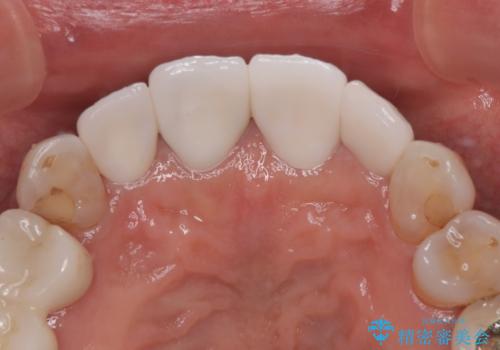

上顎前歯の歯肉ラインにエナメル質の欠損が認められ、そこが原因で冷たいものがしみている状態でした。

歯の大きさが小さいこと、隣の歯や反対側のセラミッククラウンの境目が見えていることなどから、前歯4本あるいは6本に対して、オールセラミッククラウンによる補綴治療をご提案しました。

6本同時に処置を行うと、矮小歯をより大きく見えるように工夫ができるというメリットがありましたが、4本のみの処置でも十分に満足をされていらっしゃいました。